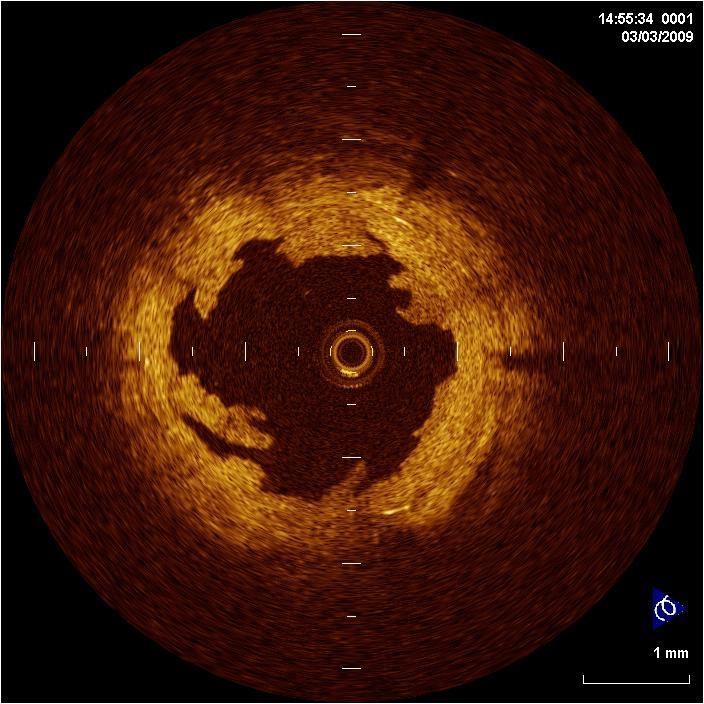

OCT